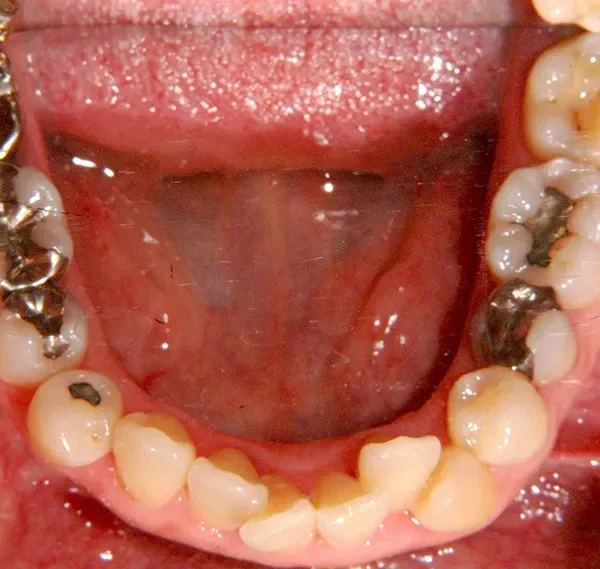

初診時年齢 40歳以上 (女性) 主訴 上下のがたがた・噛み合わない

診断名 叢生 装置名

上下のがたがたと噛み合わない事を主訴に来院されました。

歯は抜かずに矯正治療しました。

治療回数35回、2年8ヶ月の治療期間で矯正治療を終了しました。

噛み合わせが安定する事で、大きくなっていた咬筋が正常な大きさになり、顎のラインもシャープになり大変よろこばれていました。